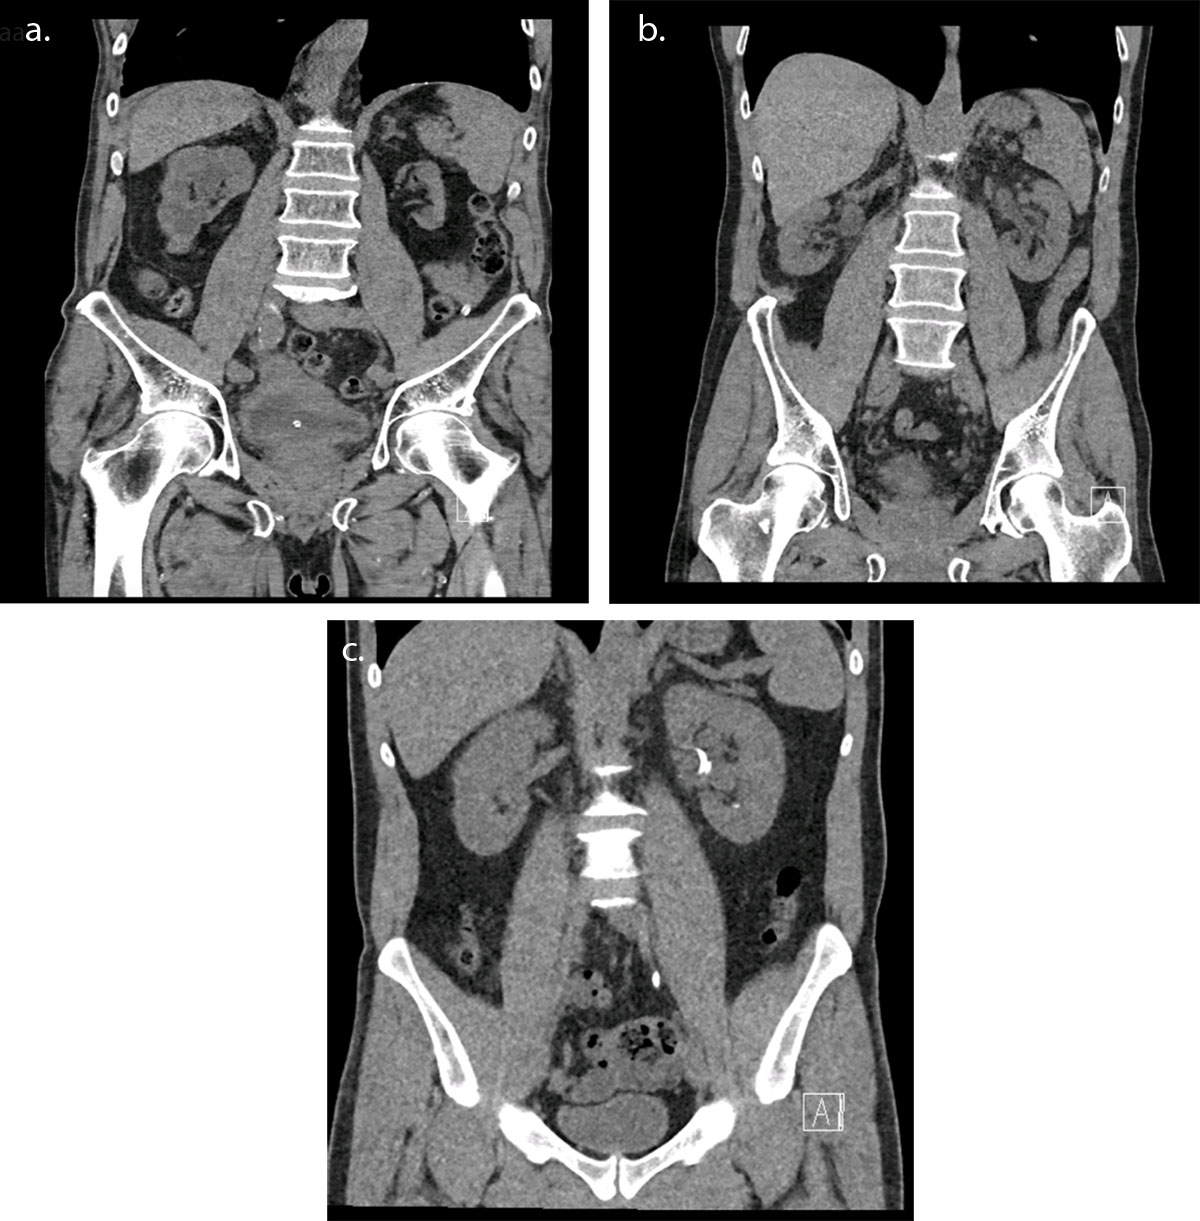

Figure 1

CT examination for urolithiasis in coronal section for three patients of similar diameters: (a) wrong acquisition length and protocol selection – DLP 206.1 mGy.cm (b) right protocol but wrong acquisition length – DLP 82.4 mGy.cm (c) right protocol selection using Tin Filter and right acquisition length – DLP 34.3 mGy.cm.